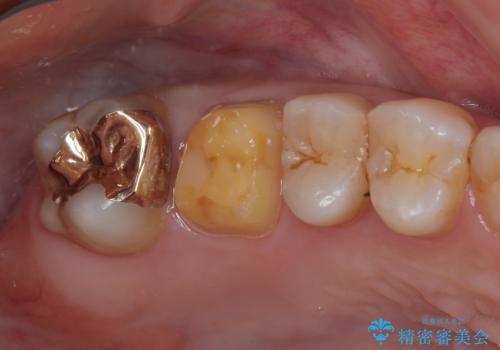

右上の6番目の歯はメタルインレーが大きかったためルジルコニアクラウン、右上の7番目の歯は一番奥で審美的な要素よりも機能面を重視してゴールドインレー修復による治療計画を立案しました。

拡大鏡視野下で保険のプラスチック(コンポジットレジン)、虫歯を除去し、フルジルコニアクラウン、ゴールドインレーに適した形にしました。

歯と歯茎の間に圧排糸と呼ばれる糸を入れてシリコーン印象を行いました。